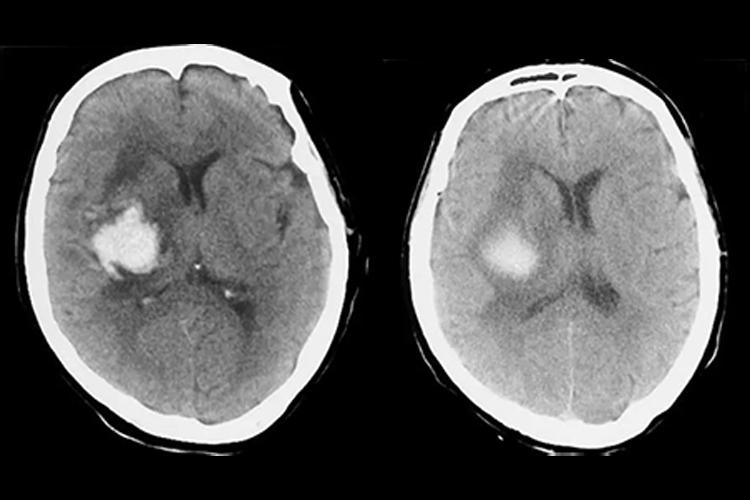

高血压病脑出血内囊出血,是指高血压脑的内囊部位出血,CT平扫可见圆形或卵圆形均匀高密度影。

内囊为脑出血最为常见的部位,当高血压病脑出血发生在内囊时,一般无法通过肉眼观察,需借助影像学检查帮助诊断,CT平扫可见圆形或卵圆形均匀高密度影,边界清楚,周围水肿呈低密度改变。